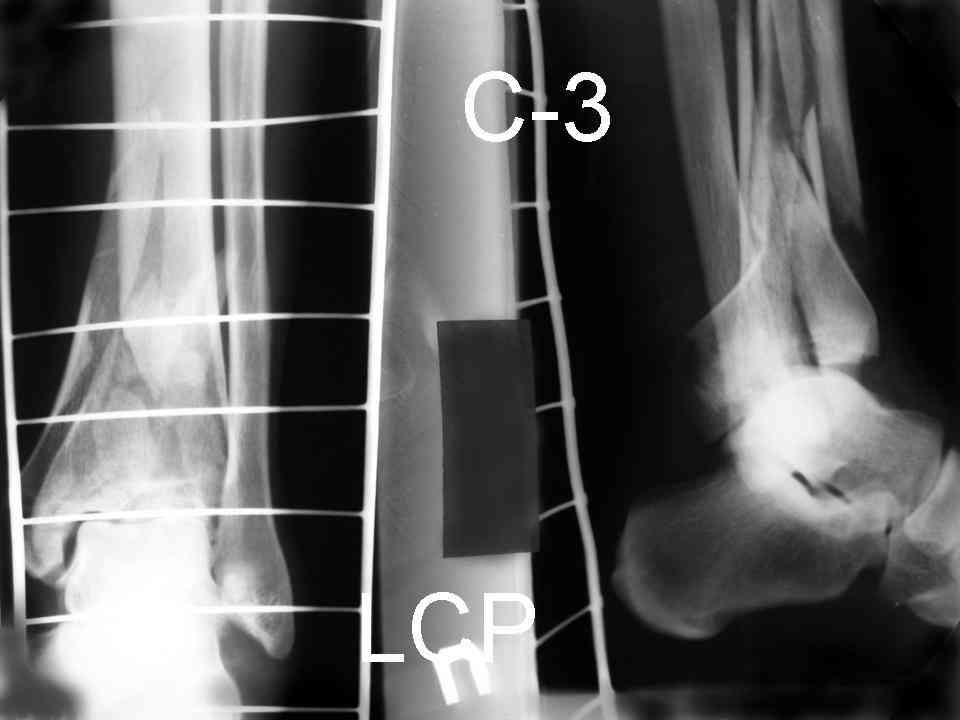

На рентгенограммах типичный перелом пилона по типу С-3. есть опыт до 100 открытых опреаций у нас в клинике. 20 примерно в год. Принцип один -все внутрисуставные переломы нуждаются в открытой репозиции и внутренней стабильной фиксации. При поступлении КТ не надо, так как получается только нагромождение костей. Истинной картины нет. Главное восстановить длину малоберцовой кости - это ключ к успеху. При поступлении меньше всего надо думать о сосудистых расстройствах, т.к. сама операция и репозиция даже сначала частичная даёт улучшение сосудитых нарушений. Причём очень быстро. Операция в 2этапа. При поступлении доступ позади наружной лодыжки, причём обязательно. После этого репозиция малоберцовой кости и фиксация пластиной 1/3 трубки под винт 3,5. Дренаж и любой аппарат наружной фиксации. Затем после спадения отёка на 5-7-10 день аппрат снимается и дугообразный разрез спереди от медиальной лодыжки 10-12 см. Главной чтобы расстояние между 1 и вторым разрезом было не меньше 7-8 см. Тогда не будет некрозов лоскутов. Таранная кость используется как матрица на неё укладываются отломки и фиксируются пицами. Ренг-контроль. Отломки лежат все отдельно, но ничего не высыпется. При переломах С-3 всегда нужна костная пластика (из крыла). Фиксация пластиной лист клевера простой или LCP. Гипс не нужен. Дренаж до 48 часов. Операция длится 3-4 часа обязательно без жгута. Посылаю примерно такой же случай.

Ещё есть одна проблема когда есть перелом малоберцовой кость, то всё ясно. А когда малоберцовая кость не повреждена, то сразу накладывается аппрат наружной фиксации при поступлении, чтобы как бы перерастянуть отломки и главное убрать вальгусное или варусное смещение, а потом на 5-7 день открыто большеберцовая кость восстанавливается и фиксируется пластиной. С уважением Дрягин

Послала ещё два снимка, если не пройдут, пошлю ещё. Дрягин. Если есть вопросы, готов ответить.